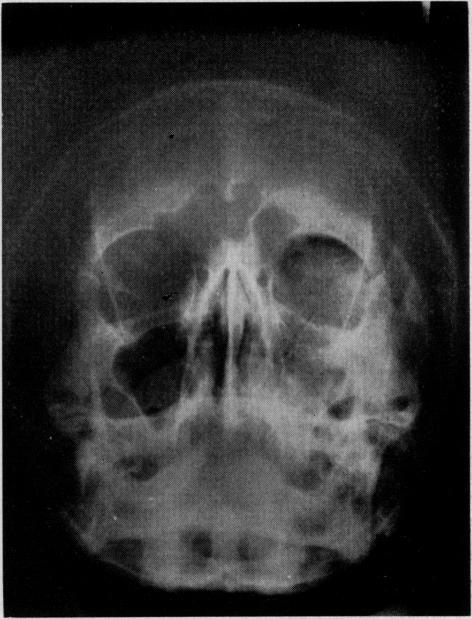

Blowout fractures of the orbit, a frequent complication of midfacial trauma, result from an increased intraorbital pressure which "blows out" the weakest area-the floor. Intraorbital fat and muscles herniated into the maxillary sinus, muscles incarcerated in the fracture, and the displaced orbital contents produce diplopia. After incarceration, elevation of the affected eye is impossible.Diagnosis is frequently difficult because initial intraorbital hemorrhage may limit mobility. Tomograms in the Waters' projection may show the fracture but frequently reveal only a cloudy antrum. The muscle traction test described herein is most helpful.The surgical correction aims at bridging the defect with Teflon or stainless-steel mesh or endogenous bone graft placed beneath the periosteum. Entry is gained through the lower lid. If repaired early, there is no functional loss and the repair is cosmetically excellent.

眼眶爆裂性骨折是面中部创伤的常见并发症,是由于眶内压力增加致使最薄弱区域——眶底“爆裂”所致。眶内脂肪和肌肉疝入上颌窦,肌肉嵌顿于骨折处,以及眶内容物移位会导致复视。嵌顿发生后,患眼无法上抬。诊断常常困难,因为最初的眶内出血可能会限制眼球活动。华氏位体层摄影可能显示骨折,但常常仅显示上颌窦模糊不清。本文所述的肌肉牵拉试验最有帮助。手术矫正旨在用置于骨膜下的聚四氟乙烯、不锈钢网或自体骨移植片来修复缺损。通过下眼睑切口进入。如果早期修复,不会有功能丧失,而且修复后的外观效果极佳。